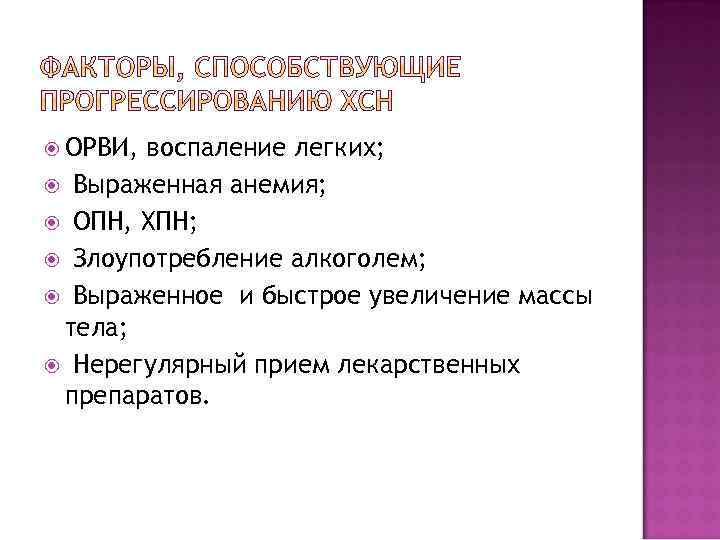

ОРВИ, воспаление легких; Выраженная анемия; ОПН, ХПН; Злоупотребление алкоголем; Выраженное и быстрое увеличение массы тела; Нерегулярный прием лекарственных препаратов.

ОРВИ, воспаление легких; Выраженная анемия; ОПН, ХПН; Злоупотребление алкоголем; Выраженное и быстрое увеличение массы тела; Нерегулярный прием лекарственных препаратов.